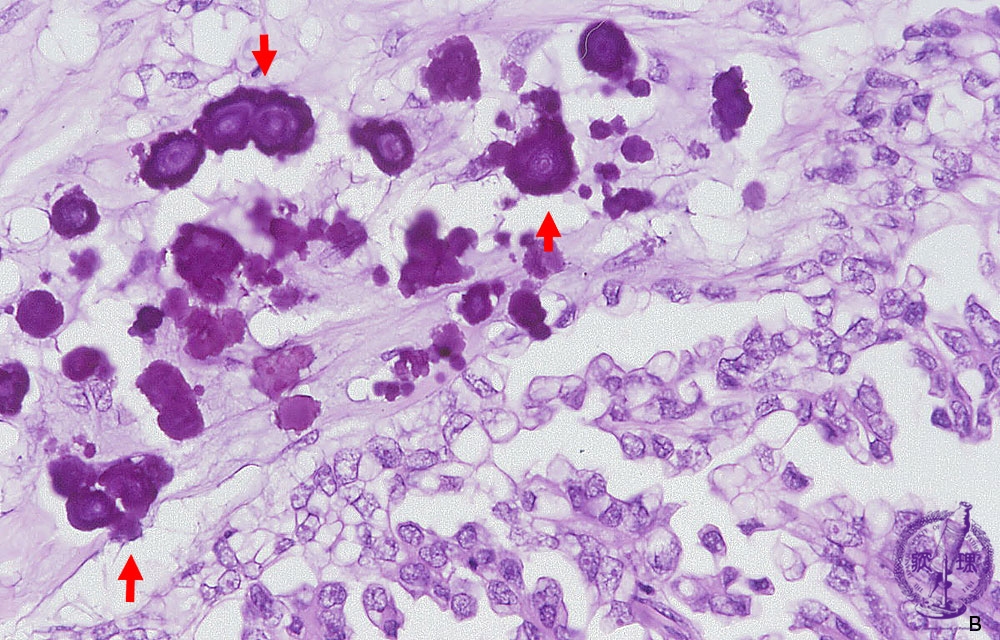

卵巣漿液性嚢胞腺癌ミクロ像(HE強拡大)

ミクロ像(HE強拡大):卵巣漿液性嚢胞腺癌。しばしば砂粒体(Psammoma body)と呼ばれる石灰沈着がみられる。